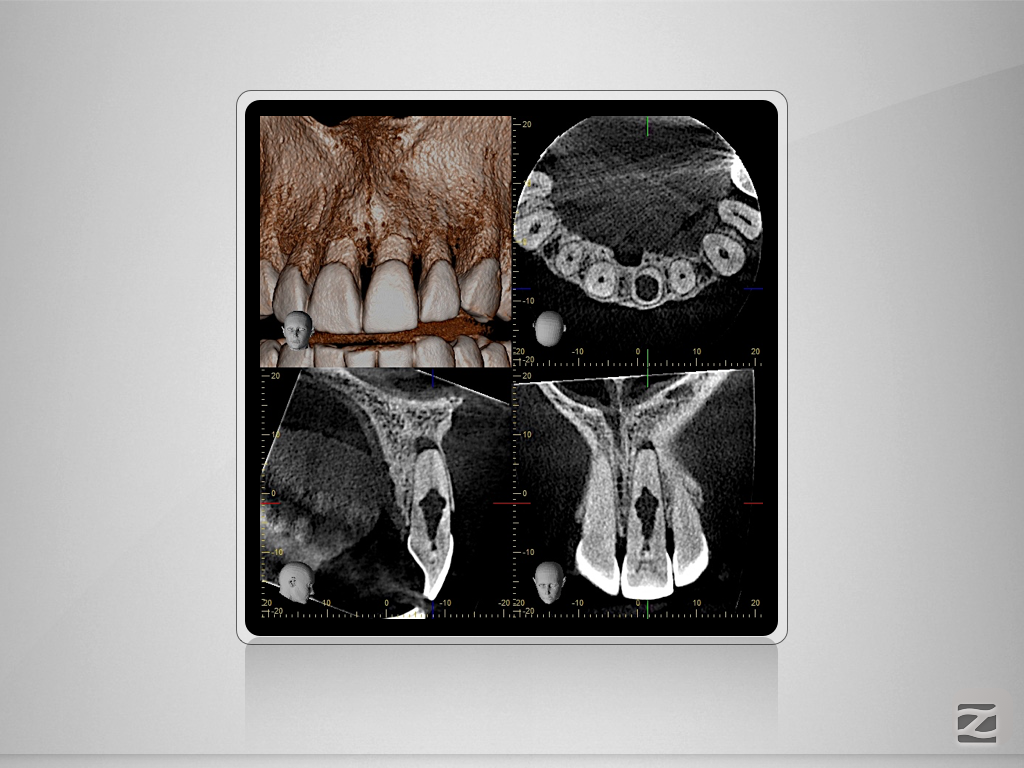

Wie eine Pulpanekrose einen Zahn retten kann.